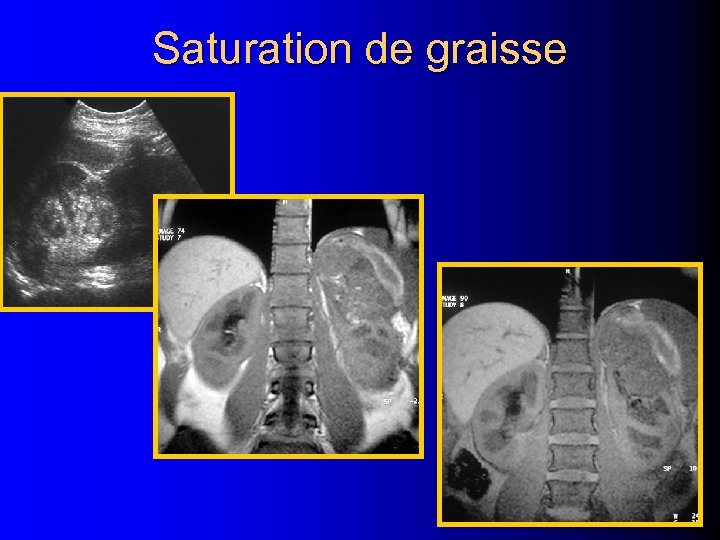

Saturation de graisse

Saturation de graisse

India Ink artifact l Perte de signal linéaire à la jonction graisse /eau – A la jonction tumeur / parenchyme – Dans la tumeur entre les plages graisseuses et non graisseuses Israel GM et al, AJR 2005; 184: 1808

India Ink artifact l Perte de signal linéaire à la jonction graisse /eau – A la jonction tumeur / parenchyme – Dans la tumeur entre les plages graisseuses et non graisseuses Israel GM et al, AJR 2005; 184: 1808